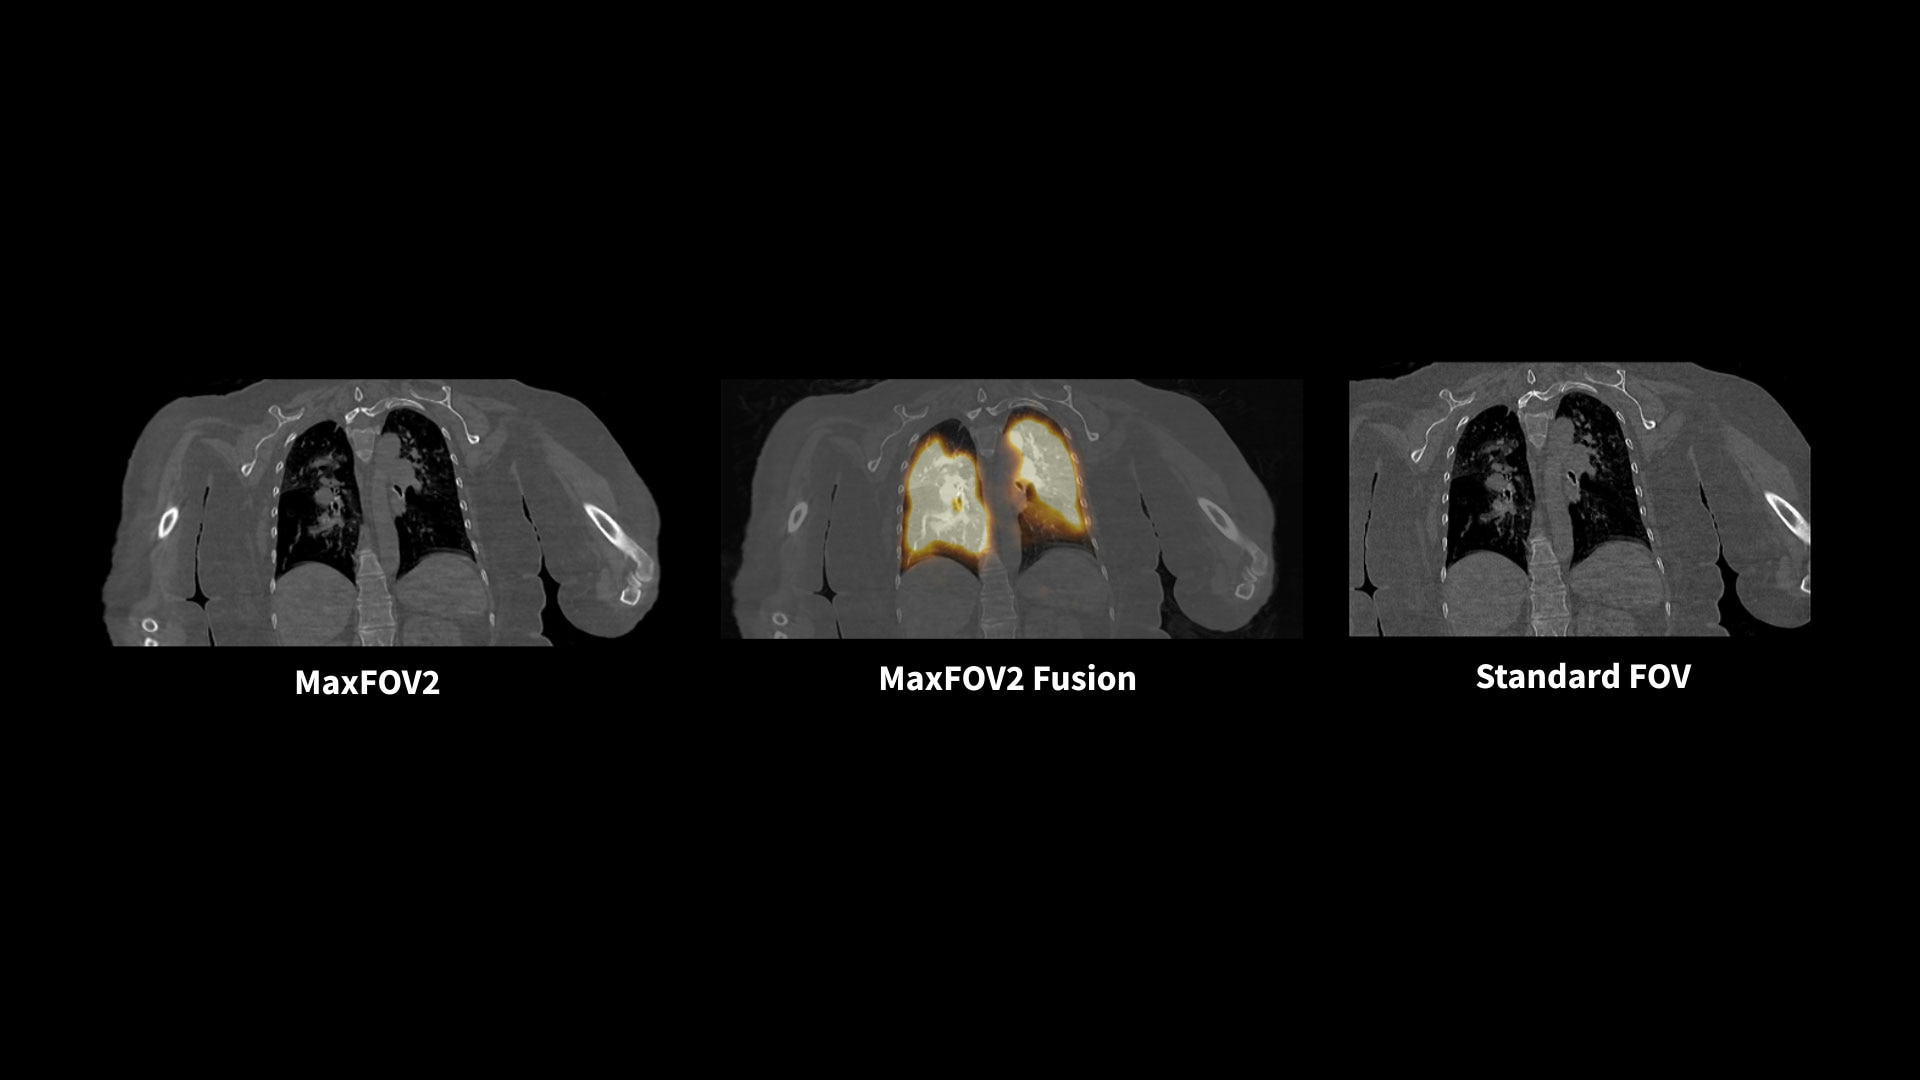

MaxFOV2* extends the display field of view (DFOV) from 50 cm to 75 cm¹⁴

When body size or positioning causes portions of the patient to extend outside the scan field of view, MaxFOV2's AI algorithm overcomes this, enabling the visualization of the patient's whole anatomy.

Aurora's 75 cm-wide CT bore opens up more space to high BMI patients for a comfortable scanning experience. The 75 cm CT display field of view with MaxFOV2* enables the visualization of high BMI patient's whole anatomy.¹⁴

14. The image quality for the area outside the standard 50 cm scan field does not meet the image quality specifications shown in the technical data sheet and image artifacts may appear, depending on the anatomy scanned.